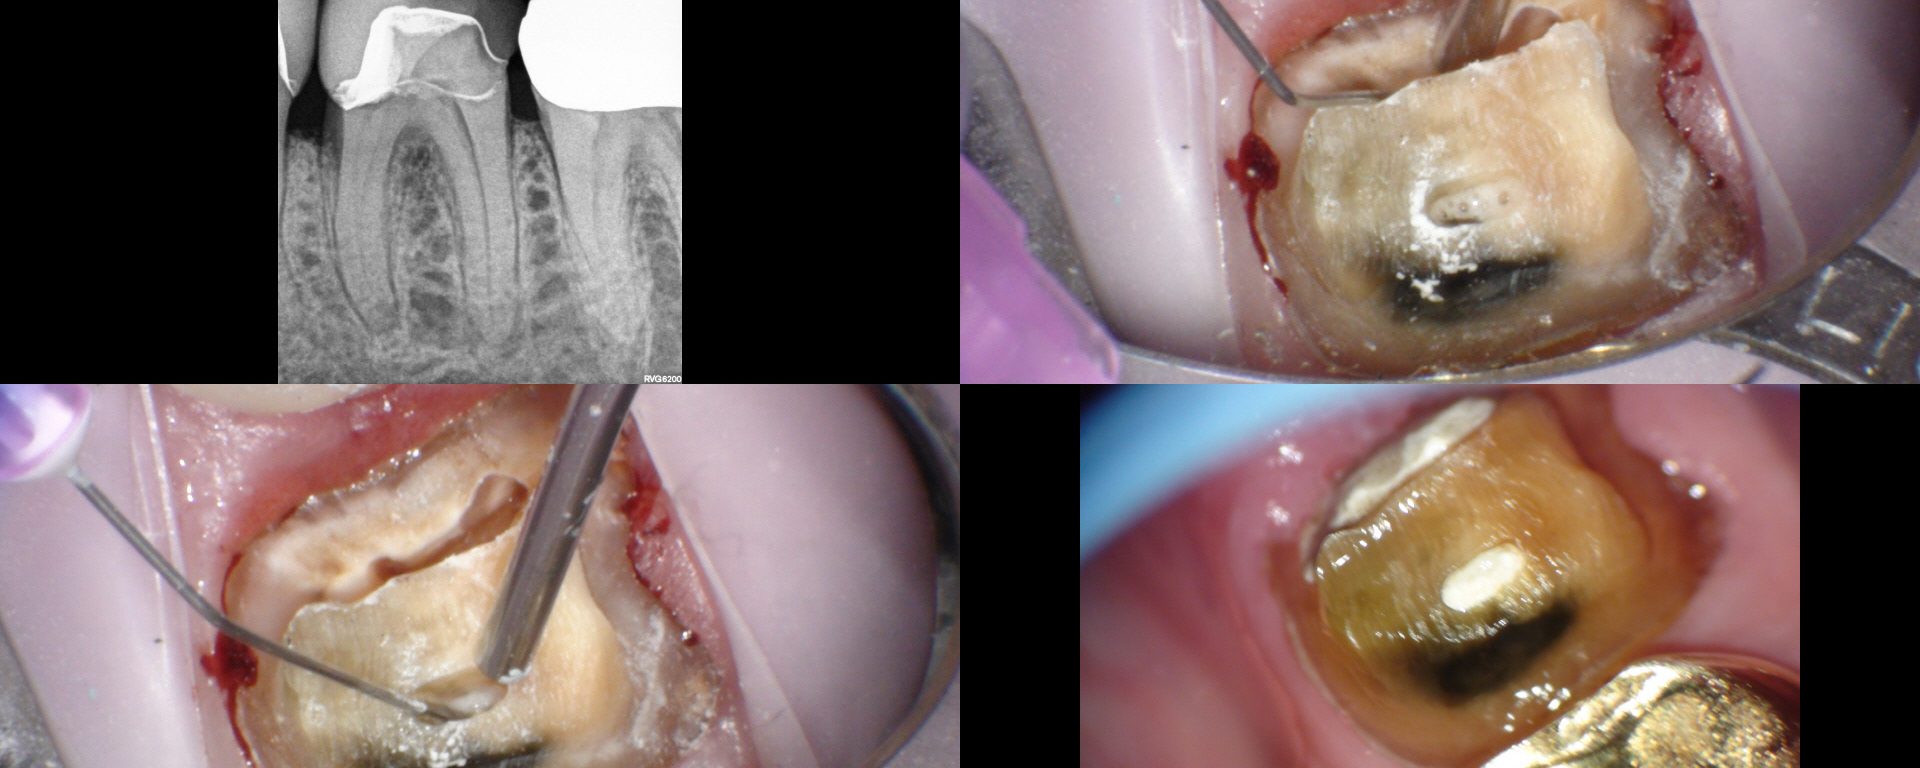

Here, traditional access would have removed most of the remaining PCD.  We leveraged the caries and existing loss of tooth structure at the mesial, and poked a hole in the distal with an EG4.  Chairside in the scope manages the field and NaOCl irrigation easily. Temporary was left off with hygiene instructions.  Tissue was healing […]